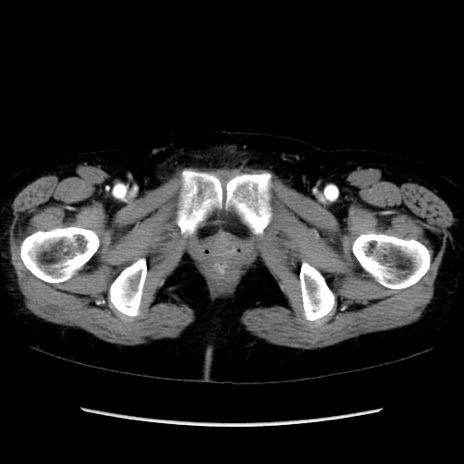

矢状断像

【症例】40歳代 女性

【主訴】上腹部痛、嘔気・嘔吐

【現病歴】約9時間前頃から急に上腹部痛、嘔気、嘔吐が出現。改善しないため救急要請。

【既往歴】子宮頚癌(広汎子宮全摘術、放射線療法)、腸閉塞

【身体所見】腹部:平坦、軟、腸雑音亢進、上腹部を中心に腹部全体に圧痛あり。

【データ】WBC 8400、CRP 0.03